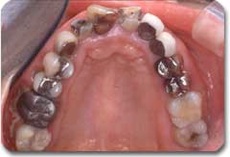

かみ合わせ治療前の状態です